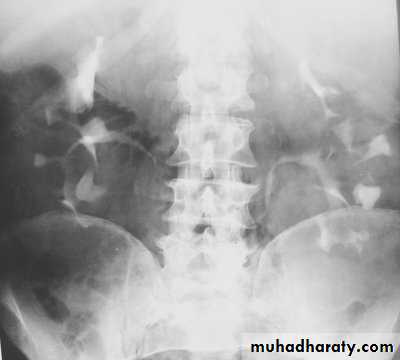

IVU :

- There is rounded or elliptical dilatation of lower end of ureter with thin lineal filling defect around it , resembling (cobra head appearance),

- Proximal dilatation of rest of ureter .

- In advanced cases hydronephrosis .

- In obstructed ureterocele , filling defect in the bladder